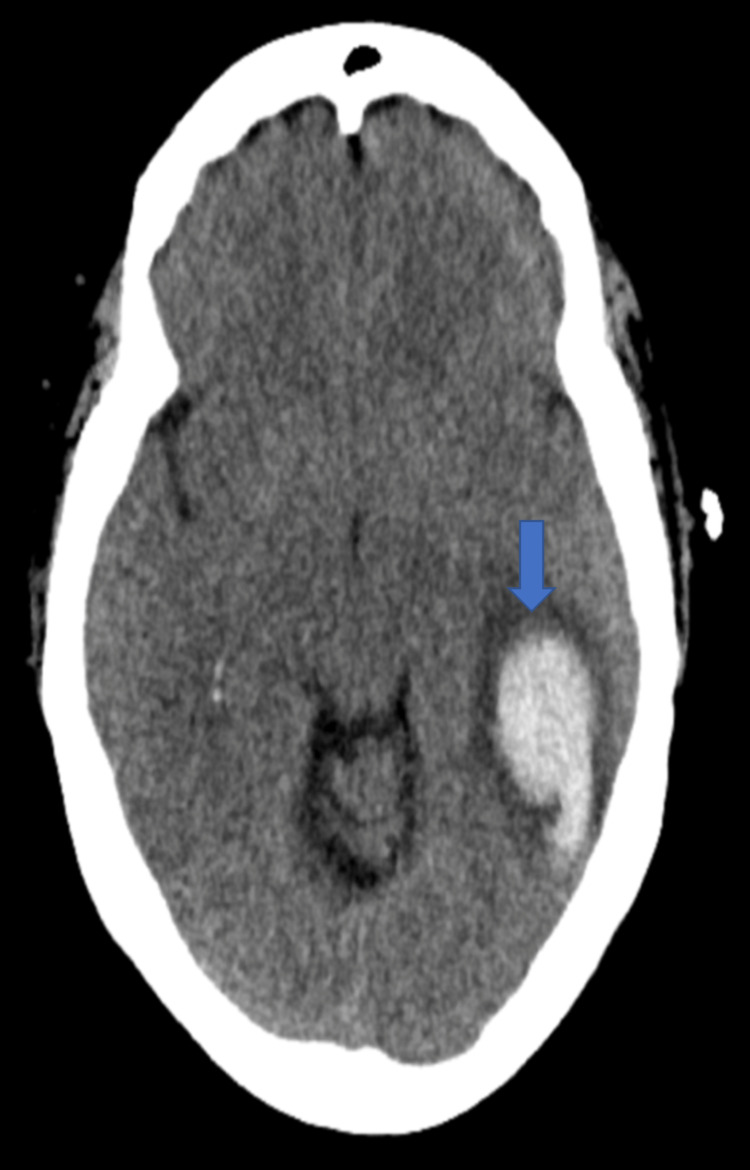

A year after her last outpatient appointment, she presented to the hospital with recurrent episodic thunderclap headaches with associated nausea, vomiting, and photosensitivity. Her neurologic examination was notable for aphasia without notable weakness. In the interim, she had established care with another neurologist who was closer to her home, who had discontinued verapamil and started the patient on venlafaxine for treatment of headaches and mood. CT Head without contrast revealed bilateral SAHs and a left frontal intraparenchymal hemorrhage, approximately 9.4 cc by ABC/2 formula (Figure 3). CTA Head and Neck with contrast again demonstrated multifocal stenosis of intracranial arteries. She underwent a second DSA, which demonstrated multifocal stenosis of intracranial arteries bilaterally (Figures 4–5). Angiogram found diffuse irregularities primarily affecting bilateral anterior cerebral arteries and, to a lesser extent, the bilateral middle cerebral and right superior cerebellar arteries. The patient also underwent brain biopsy with hematoma evacuation. Rheumatological workup was repeated and unremarkable. Lumbar puncture was performed and notable for mildly elevated glucose of 85 (normal range: 50-75 mg/dL) and mildly elevated protein at 46 (normal range: 15-45 mg/dL). Due to concern for PACNS as per discretion of treating physician at that time given the recurrence of symptoms and vascular irregularities, she was administered one dose of high-dose IV methylprednisolone, but this was discontinued when brain biopsy was planned. The biopsied temporal artery, dura, and brain showed no evidence of vasculitis. In the absence of any evidence for an ongoing inflammatory process, verapamil was restarted for symptomatic treatment of suspected recurrent RCVS. It was felt that RCVS was likely precipitated to exposure to SNRI. Venlafaxine was discontinued as this is a known precipitant of RCVS. After clinical improvement, the patient was discharged home and advised to continue verapamil, follow up with vascular neurology outpatient clinic, and undergo follow-up repeat vessel imaging.

Unfortunately, she returned to the hospital one week later with new onset right facial weakness and receptive aphasia. CT Head without contrast now revealed an acute left temporal lobe hemorrhage approximately 5.5 cc by ABC/2 formula (Figure 6). CTA Head and Neck with contrast demonstrated increased multifocal irregularities compared to prior imaging studies. Patient’s home dose of verapamil was increased. The patient improved clinically and at the time of discharge, she had residual receptive aphasia and trace right facial weakness. There was suspicion that the patient was using medical marijuana for symptomatic relief of headache pain as per collateral obtained from patient’s family. At the time of discharge, the patient was extensively counseled to avoid all possible precipitants of RCVS.